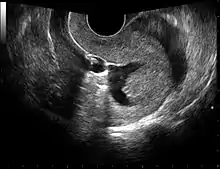

Gynecologic ultrasonography or gynecologic sonography refers to the application of medical ultrasonography to the female pelvic organs (specifically the uterus, the ovaries, and the fallopian tubes) as well as the bladder, the adnexa, and the recto-uterine pouch. The procedure may lead to other medically relevant findings in the pelvis.This technique is useful to detect myomas or mullerian malformations.

The examination can be performed by transabdominal ultrasonography, generally with a full bladder which acts as an acoustic window to achieve better visualization of pelvis organs, or by transvaginal ultrasonography with a specifically designed vaginal transducer. Transvaginal imaging utilizes a higher frequency imaging, which gives better resolution of the ovaries, uterus and endometrium (the fallopian tubes are generally not seen unless distended), but is limited to depth of image penetration, whereas larger lesions reaching into the abdomen are better seen transabdominally. Having a full bladder for the transabdominal portion of the exam is helpful because sound travels through fluid with less attenuation to better visualize the uterus and ovaries which lies posteriorly to the bladder. The procedure is by definition invasive when performed transvaginally. Scans are performed by health care professionals called sonographers, or gynecologists trained in ultrasound.